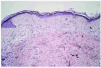

Fig. 3.--Control histopatológico sin signos de infiltración tumoral después del tratamiento.